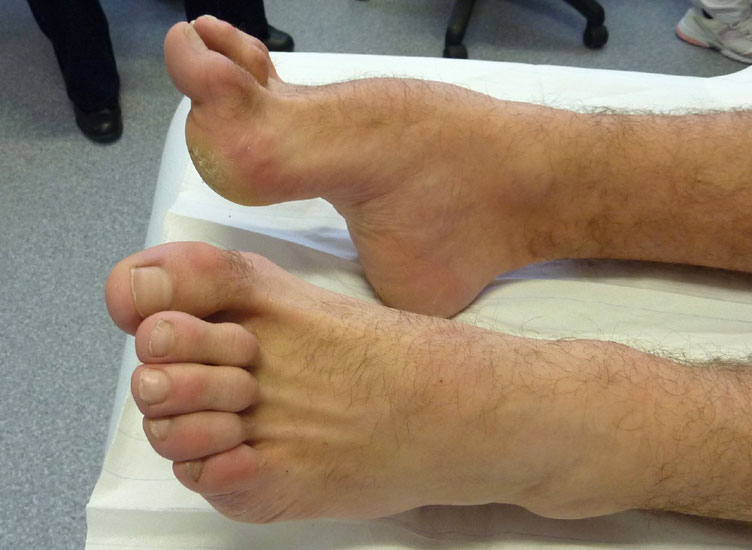

a) Inspektion

Inspektion des Patienten mit entkleideten Beinen (nicht nur mit hochgezogener Hose):

Inspektion im Stand

• von vorne

• von beiden Seiten

• von hinten

Folgende Befunde werden erhoben:

• Beinachse

• Form der Füße

• Morphologie der Beinmuskeln (Seitendifferenz, Waden distal dünn (Abb. 11), Narben)

Inspektion im Liegen von plantar

• Beschwielung

• plantare Prominenzen